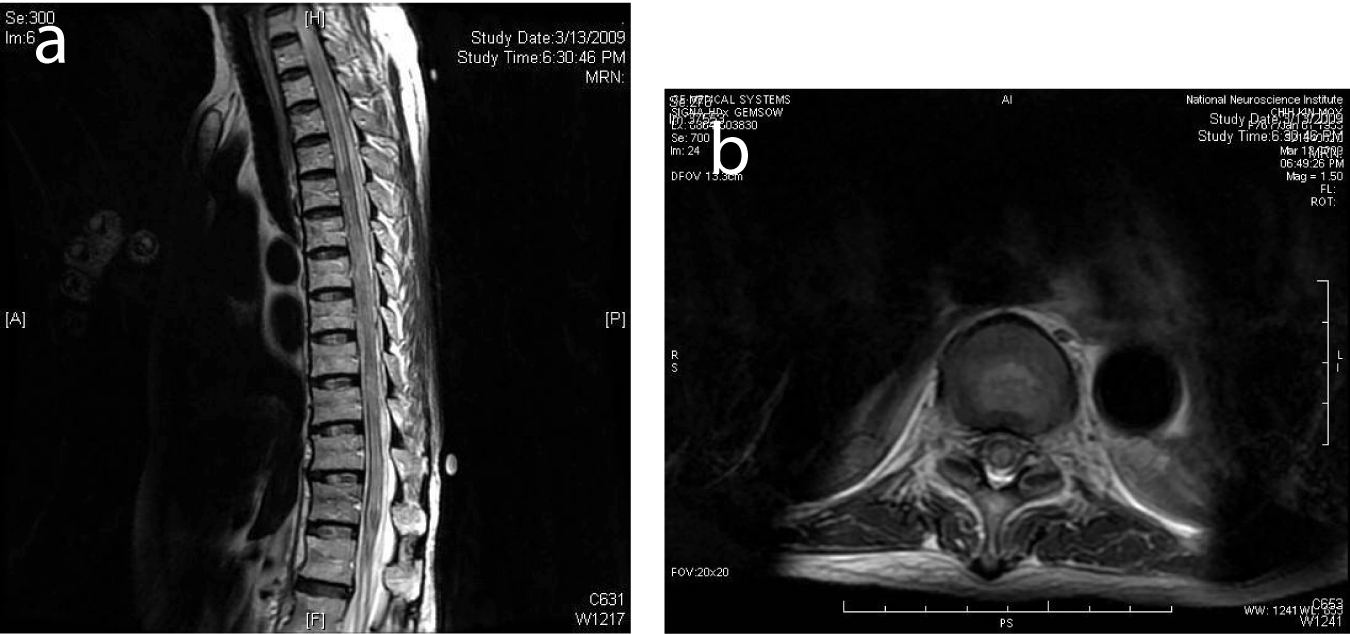

Differential diagnoses considered included lymphomatous infiltration of the spinal cord, leptomeningeal spread, cord compression from pathological vertebral fracture, and possibly spinal cord or meningeal infection. Intracranial metastases were also considered. Initial investigations did not indicate any specific etiology. Hemoglobin was 10.7 g/dL. Mild leucocytosis was noted. Serum calcium was slightly raised at 2.7 mmol/L. Hyponatremia was noted with serum sodium of 126 mmol/L. Renal, liver and thyroid function was normal. Serum lactate dehydrogenase was elevated above 3000 U/L likely related to tumour bulk. Chest X-ray was normal. Bone marrow biopsy did not reveal lymphomatous infiltrates. More notable, MRI of the brain and whole spine did not show any acute intracranial or spinal cord abnormality (Fig. 1). Cerebrospinal fluid (CSF) analysis showed cell count, protein and glucose levels within normal limits. No malignant cells were detected. Nevertheless our patient was given a course of intravenous dexamethasone for a presumptive malignant cord compression. Repeat CSF analysis three days later was again normal. Decision was made to proceed with first cycle of chemotherapy (R-CHOP), four days after presentation.

![]() Click for large image | Figure 1. (a) Selected sagittal MR image of the thoracic spine on initial presentation showed normal cord signal. (b) Cervical cord on presentation showed normal MR signal. |